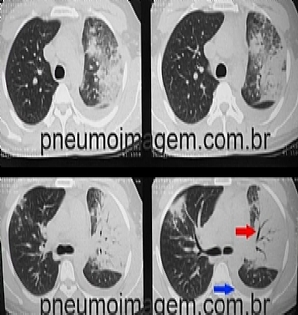

Veja imagens de Pneumonia

clicando aqui.